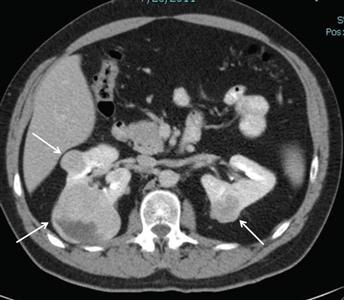

Approximately 25% to 35% of individuals with BHD develop renal tumors,[1,4,10,11] which are multifocal in 65% of cases and often bilateral. The frequency of renal tumors among patients with BHD whose medical records were reviewed was 20%, and the frequency of renal tumors among BHD patients evaluated by CT scan was 29%. Most renal tumors associated with BHD are slow growing. Median age at diagnosis is 48 to 50 years (range, 31–71 y).[2,12,13,14] Men developed renal tumors more often than did women (27 males; 11 females). Renal tumors associated with BHD seem to occur at a younger age than do sporadic forms of renal cell cancer (RCC), in which the median age at diagnosis is 64 years.[15]Figure 1 depicts bilateral renal tumors in a patient with BHD.

Axial view of an individual's midsection showing two tumors in the left kidney and one tumor in the right kidney.

Figure 1. Birt-Hogg-Dubé syndrome–associated renal tumors are commonly multifocal and bilateral. Arrows indicate the locations of the tumors.